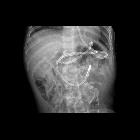

Toddler after

feeding tube placementAXR shows a feeding tube entering the stomach and then looping back upon itself into the proximal esophagus.The diagnosis was feeding tube malfunction due to placement of the feeding tube tip in the esophagus.